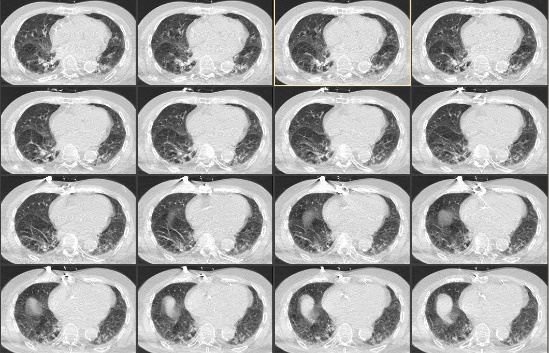

1 资料与方法病例1,男性,87岁,因“洗澡后突发头痛,呕吐半天”急诊入院。既往史有高血压病史数十年,血压控制良好;冠心病史,2007年接受“冠脉搭桥术”,长期服用拜阿司匹林325 mg 1次/d,辛伐他汀80 mg 1次/晚。入院查体:格拉斯哥昏迷评分法(Glasgow Coma Scale,GCS)14分,双瞳等大等圆,光敏,四肢肌力正常,双侧病理征阴性。入院头颅CT(图 1)示小脑蚓部血肿,量约7 mL,四脑室和环池清晰;双侧额顶叶,脑室旁多发缺血腔隙灶,脑萎缩。CTA提示未见明显异常。

| 图 1 2007年5月11日患者入院第1天头颅CT |